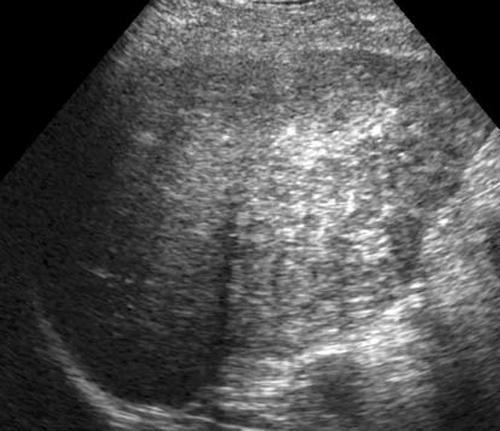

Cirrhosis

nodular and course

heterogenic

Ascites

Cirrhosis

nodular and course

heterogenic

Ascites